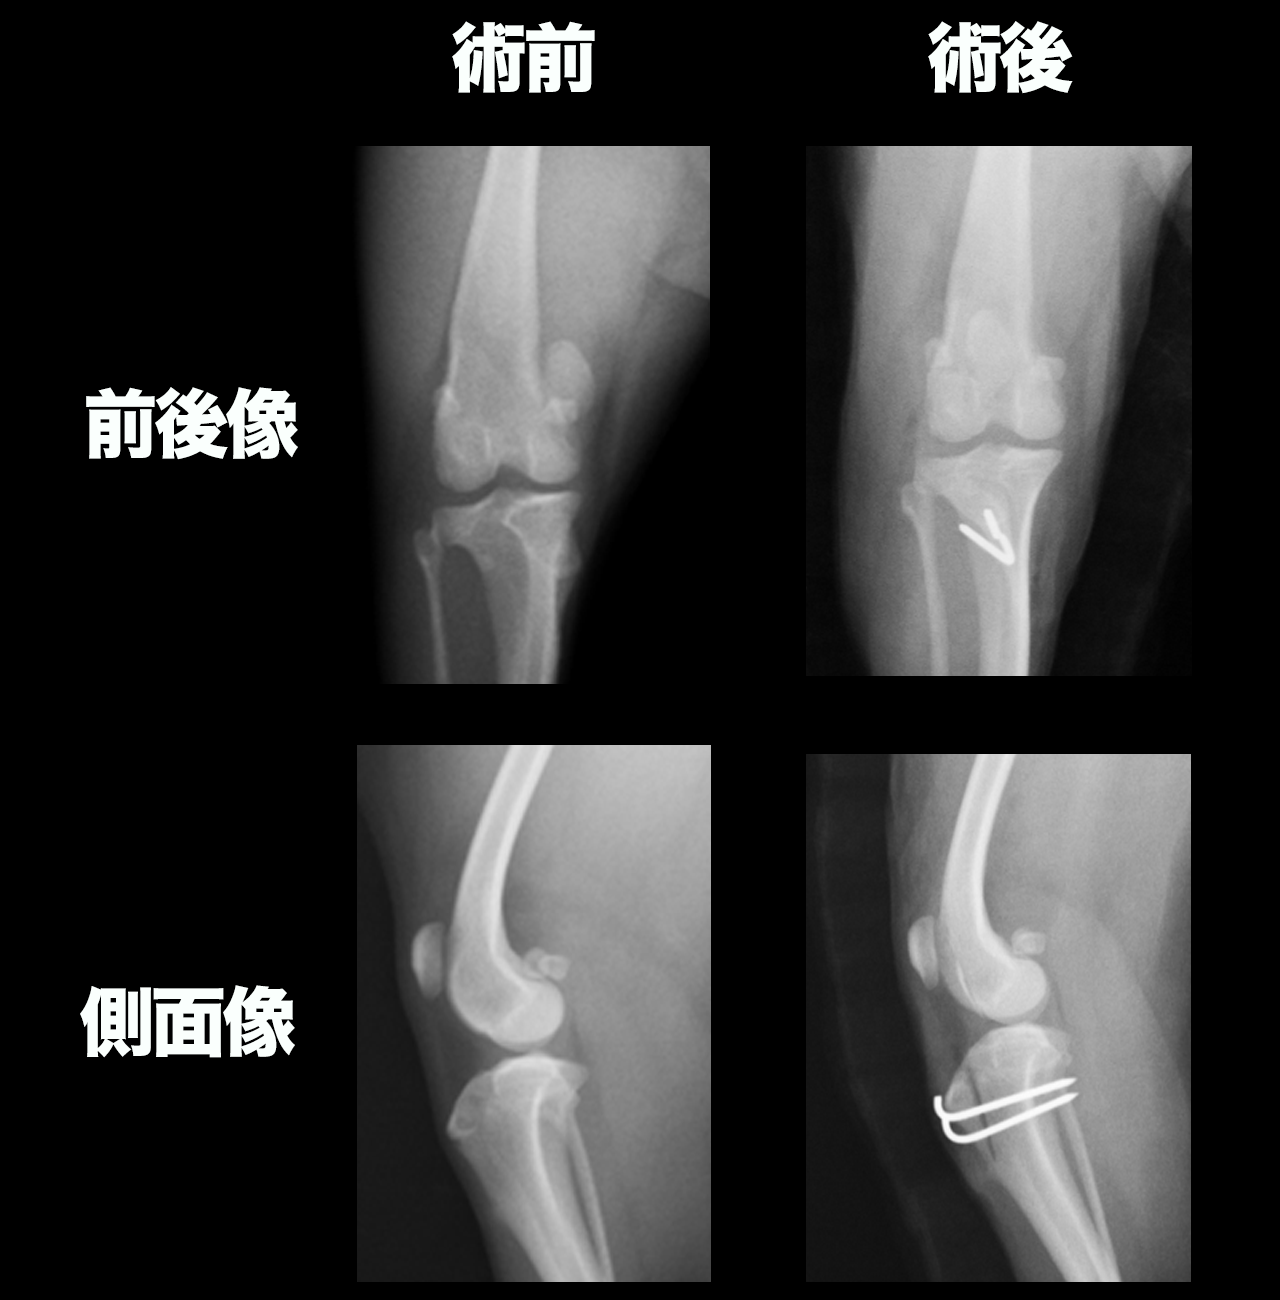

手術の考え方

膝蓋骨内方脱臼の手術では、単に膝蓋骨を元の位置に戻すだけでは不十分です。重要なのは、大腿四頭筋機構の整列を是正し、膝蓋骨が滑車溝内で安定して動くように再建することです。

症例に応じて、以下の術式を組み合わせます。

- 脛骨粗面転位術

内側に変位した脛骨粗面を外側へ移動させ、膝蓋靱帯の牽引方向を正常化します。

膝蓋骨脱臼の矯正で非常に重要な術式のひとつです。

- 矯正骨切り術

大腿骨や脛骨の変形を伴う症例では、骨そのものの軸を矯正する手術が必要になることがあります。

特に重度の症例では、矯正の有無が治療成績を左右します。

術後管理

術後は、術者の判断により3〜14日程度、ロバートジョーンズ包帯を装着することがあります。

また、骨の治癒を待つため、術後3ヶ月は運動制限が必要です。この期間は、基本的に散歩には行かず、段差の昇降や激しい運動、滑りやすい床での活動は避けます。